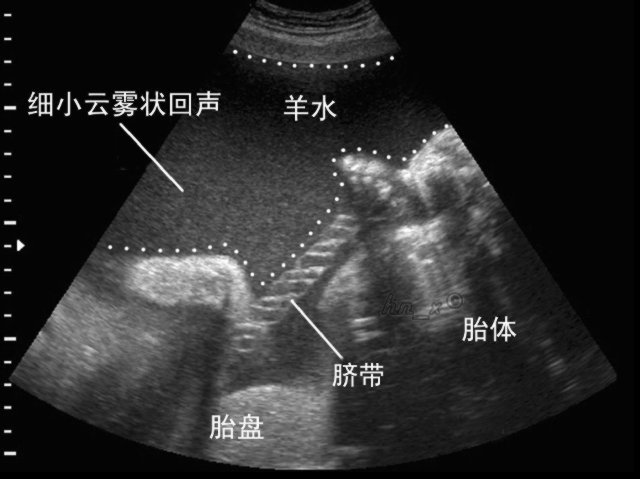

是指怀孕时子宫羊膜腔内的液体。在整个怀孕过程中,它是维持胎儿生命所不可缺少的重要成分。在胎儿的不同发育阶段,羊水的来源也各不相同。在妊娠第一个三月期,羊水主要来自胚胎的血浆成分;之后,随着胚胎的器官开始成熟发育,其他诸如胎儿的尿液、呼吸系统、胃肠道、脐带、胎盘表面等等,也都成为了羊水的来源。

羊水深度是指,B超检查表示最大羊水池的垂直深度,小于2cm表示羊水过少,大于8cm表示羊水过多。 它为医学专业名词,是判断羊水多少的一个重要指标。羊水多,则胎儿可以健康成长;羊水少,就可以在胎儿临产期造成胎粪淤积,甚至早产或窒息。B超检查表示最大羊水池的垂直深度,羊水深度3-8cm为正常羊水量。小于3cm提示羊水过少,大于8cm提示羊水过多。

羊水指数:是将子宫分成左上,右上,左下和右下四个象限,四个象限的最大羊水暗区垂直深度之和为AFL,若AFL大于24cm诊断为羊水过多,若AFL在18-24cm之间时为可疑羊水过多或羊水偏多。

羊水测量:羊水量的测量,是评估怀孕正常与否的重要指标。但隔了一层肚皮,我们实在很难正确地去评估羊水的多少。

目前,医院大多是通过超音波来了解羊水量的状况,采取"羊水指数法"来确定羊水量是否正常。方法是:将子宫分为四个象限,分别量每个象限中羊水的最大深度,再相加求其总和。总和值在8~27厘米的范围之内属于正常状态,小于8为羊水过少,大于24则为羊水过多。